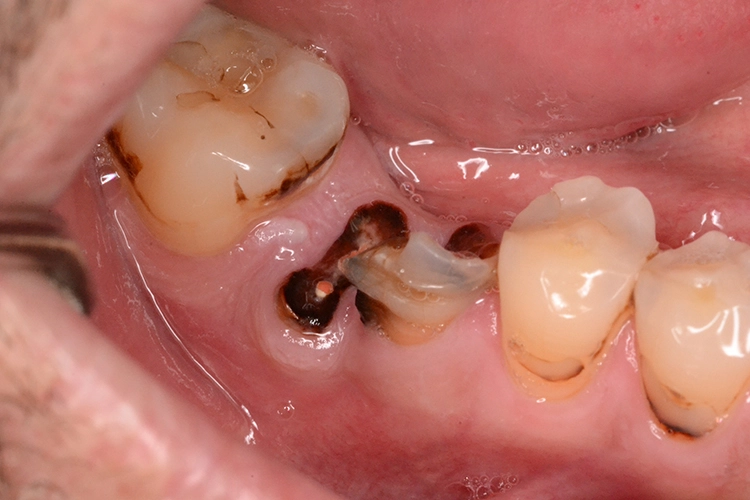

3. Sofortimplantation mit vestibulärem Knochendefekt

Im präoperativ angefertigten DVT (Abb. 3b und c) zeigte sich um die Wurzelspitze ein chronisches Entzündungsgeschehen, welches die vestibuläre Lamelle im apikalen Wurzelbereich des Zahnes 23 komplett aufgelöst hat. Da jedoch der Bereich direkt apikal von 23 nicht vom Geschehen betroffen war, fiel die Entscheidung zur Sofortimplantation auch, da der Patient blutverdünnende Medikamente einnehmen musste, welche durch Kombination von Extraktion und Implantation nur einmal abgesetzt werden mussten. In diesem Fall war aufgrund des Knochendefektes die Bildung eines Volllappens mit Entlastung unumgänglich.

Anschließend wurde der Knochendefekt mit kortikospongiösem Knochengranulat aufgefüllt und mit einer langsam resorbierenden Kollagenmembran versorgt (Abb. 3e und f). Das OP-Gebiet musste im Anschluss aufgrund der Augmentation vollständig gedeckt werden (Abb. 3g).